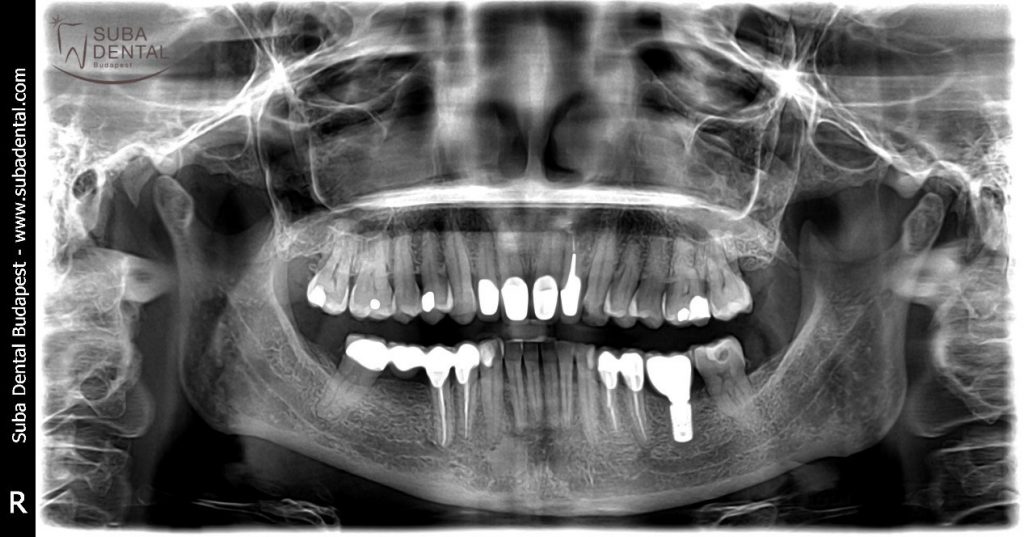

L’implant a été posé le 28 novembre 2017.

L’implant posé dans la position 36 est bien visible sur la radio panoramique de contrôle

L’implant posé dans la position 36 avec la couronne transvissée sur l’implant.